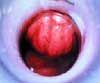

Patients with internal hemorrhoids present differently than do patients with symptomatic external hemorrhoids. Symptoms may include bleeding, protrusion, fecal soiling, and itching. Because the columnar mucosa involved in internal hemorrhoids lacks nerve endings, pain is typically not present. If a patient with enlarged internal hemorrhoids complains of pain, look for another source. Internal hemorrhoids often coexist with external hemorrhoids (Figure 3).

Initial treatment consists of conservative therapy, such as psyllium or other bulking agents, avoidance of straining, and decreased time in sitting on the toilet. Invasive therapy is indicated in patients for whom conservative management fails or who do not wish to wait for their symptoms to resolve. Grade 1 hemorrhoids are rarely symptomatic but may be effectively treated with injection sclerotherapy or rubber band ligation. Grade 2 and grade 3 hemorrhoids can be treated in the office with rubber band ligation (Figures 4 and 5). Very large grade 3 and grade 4 hemorrhoids require either surgical or stapled hemorrhoidectomy.2